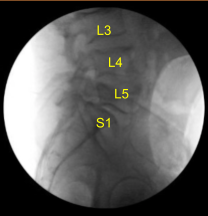

Bovie monopolar was used to carry the incision down through the midline subcutaneous tissues sharply dividing the fascia, and subperiosteal dissection with Bovie and Cobb elevators were performed exposing posterior elements of the spine at L4, L5, and S1 including bilateral transverse processes of L4 and L5, and bilateral S1 ala. During exposure, there was a small incidental durotomy noted at S2-S3 level.

We began the laminectomy and decompression. We began with the L5 decompression, bilateral pars defects were identified as per the preoperative imaging. Leksell rongeur, Kerrison rongeurs, and electric high-speed drill were used to perform L5 laminectomy and facetectomy was performed which was complete on the left side including the inferior articular process and the superior articular process.

In order to access the L5-S1 disc space, we had to remove the entirety of the L5 and S1 facet on the left side, part of the pedicle, and performed L4 laminectomy.